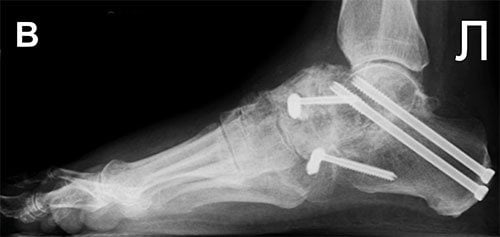

Хирургия

Если консервативная медицина остается бессильной перед артрозом таранно-пяточного сустава, то больному приходится соглашаться на хирургическую операцию. Этот вид лечения показан при заболевании последней стадии, когда дистрофия сочленения стала необратимой. Решение о проведении операции принимает врач.

Хирургическое лечение позволяет получить хорошие результаты: устраняет боль и возвращает пациента к обычной повседневной жизни. Суть оперативного вмешательства состоит в удалении из сустава всех поврежденных дистрофией фрагментов и создании благоприятных условий для его последующего сращивания. Операция проводится под общим наркозом.

Через 2 месяца человеку делают контрольный рентгеновский снимок и, если процесс заживления протекает хорошо, повязку снимают и меняют ее на ортопедический ботинок. С ним прооперированное сочленение можно понемногу нагружать, но оно будет надежно защищено от перегрузок. Контрольные снимки делают каждый месяц. Начиная с третьего месяца, врач разрешит заниматься лечебной физкультурой. Пренебрегать комплексом упражнений не стоит: занятия вернут активность и исправят проблему с развившейся после болезни хромотой.